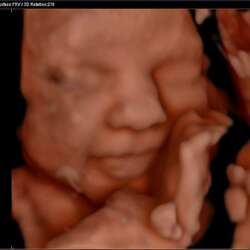

Ik had ook bruin verlies. Zelfs naar de vk geweest voor echo en was een zwangerschap te zien. Daarna kreeg ik wat roder verlies en na het weekend weer naar de vk. Toen werd gezegd dat ze niks konden vinden op de echo en ik een mk had gehad. Ik moest in de loop vd week nog test doen, die teststreep was dikker dan de controle streep! Ik voelde me ook nog zwanger en had geen stolsels verloren en ook geen grote hoeveelheid bloed, alleen bij afvegen. Daarna second opinie gedaan bij andere praktijk en hartje klopte gewoon. Inmiddels 32 weken zwanger.